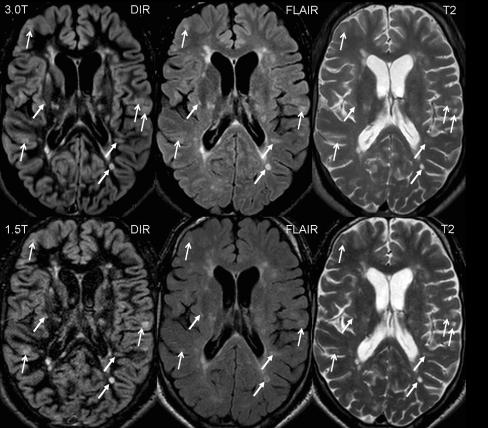

To investigate the impact of a higher magnetic field strength of 3 Tesla (T) on the detection rate of cortical lesions in multiple sclerosis (MS) patients, in particular using a dedicated double inversion recovery (DIR) pulse sequence.

Thirty-four patients with clinically isolated syndromes or definite MS were included. All patients underwent magnetic resonance imaging (MRI) at 1.5 T and 3 T, including T2-weighted turbo spin echo (TSE), fluid-attenuated inversion recovery (FLAIR) and DIR sequences. All images were analysed for focal lesions categorised according to their anatomical location.

The total number of detected lesions was higher at 3 T across all pulse sequences. We observed significantly higher numbers of lesions involving the cortex at 3 T using a DIR sequence. DIR at 3 T showed 192% more pure intracortical (p < 0.001) and 30% more mixed grey matter-white matter lesions (p = 0.008). No significant increase in cortical lesions could be detected on the FLAIR and T2-weighted images. Using the T2-weighted and FLAIR sequences, significantly more lesions could be detected at 3 T in the infratentorial, periventricular and juxtacortical white matter.

DIR brain MR imaging at 3 T substantially improves the sensitivity of the detection of cortical lesions compared with the standard magnetic field strength of 1.5 T.

研究磁场强度为 3 特斯拉(T)对多发性硬化症(MS)患者皮质病变检出率的影响,特别是使用专用双反转恢复(DIR)脉冲序列。

纳入 34 例临床孤立综合征或明确 MS 患者。所有患者均在 1.5T 和 3T 行磁共振成像(MRI)检查,包括 T2 加权快速自旋回波(TSE)、液体衰减反转恢复(FLAIR)和 DIR 序列。所有图像均根据解剖位置进行局灶性病变分类分析。

在所有脉冲序列中,3T 检测到的病变总数均较高。使用 DIR 序列时,我们观察到 3T 时皮质病变数量显著增加。3T 下的 DIR 序列显示,单纯皮质内病变增加了 192%(p<0.001),灰质-白质混合病变增加了 30%(p=0.008)。FLAIR 和 T2 加权图像上未检测到皮质病变的显著增加。在使用 T2 加权和 FLAIR 序列时,3T 下后颅窝、脑室周围和皮质下白质的病变数量显著增加。

与标准磁场强度 1.5T 相比,3T 的 DIR 脑 MRI 可显著提高皮质病变的检出敏感性。